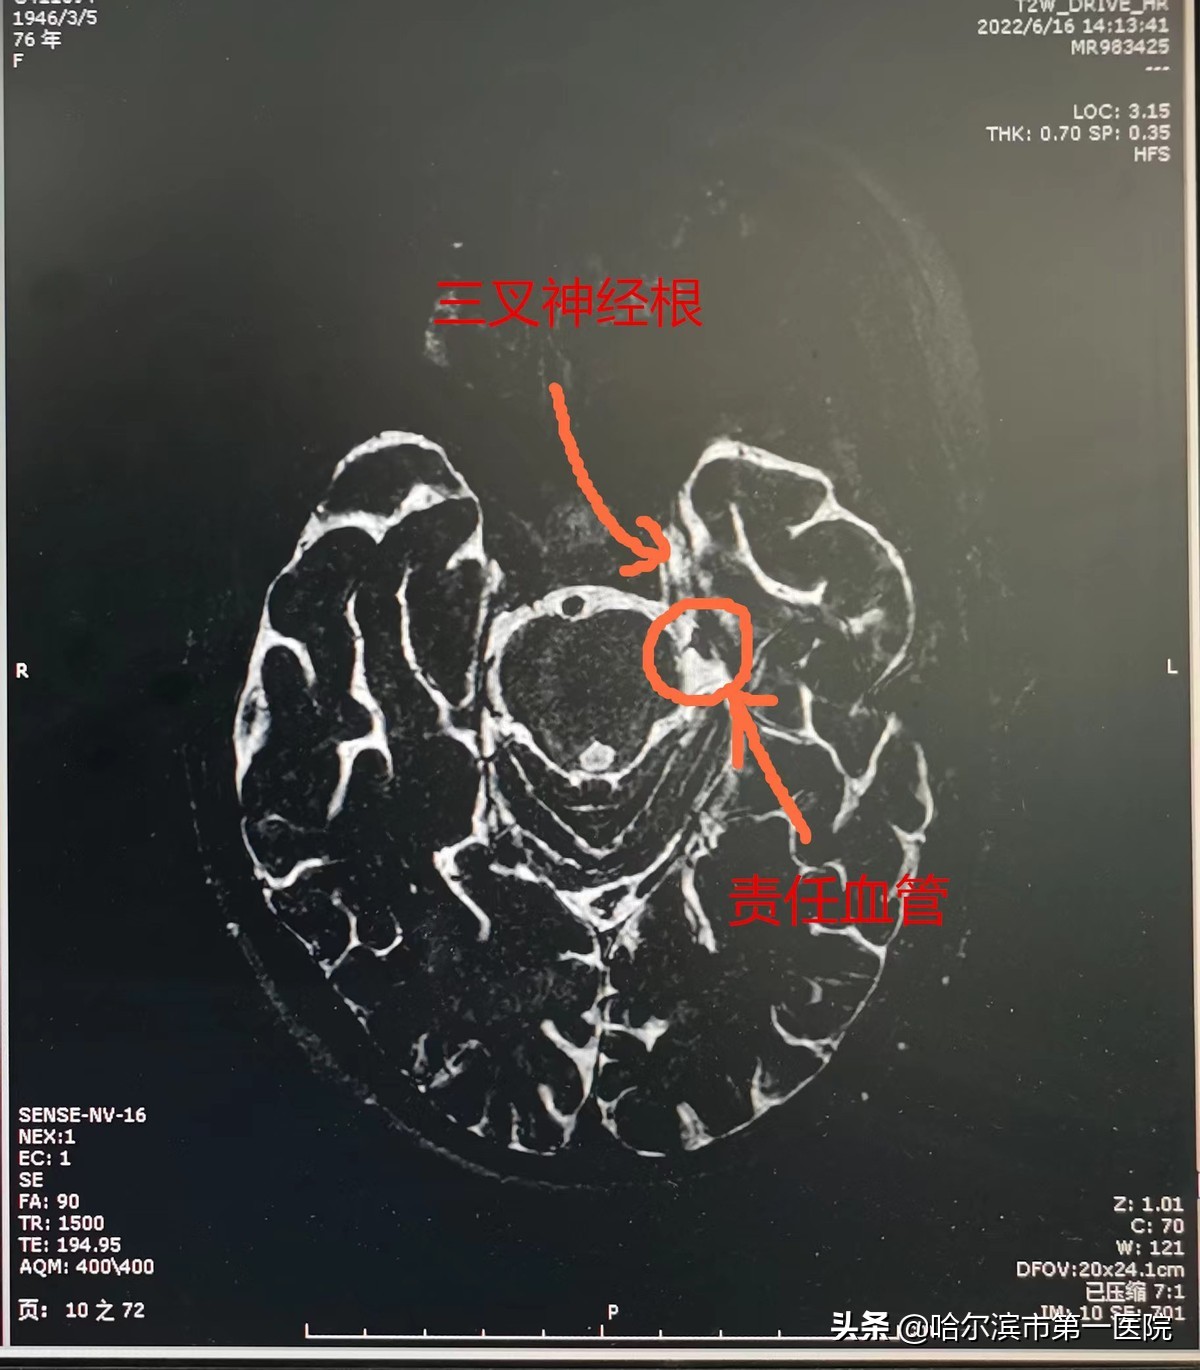

经查体发现冯大娘:左侧面部三叉神经上颌支,下颌支区感觉减退,磁共振水成像示左侧三叉神经根处可见责任血管通过,有血管压迫神经可能。为了使患者能够摆脱神经痛的困扰,在同患者家属充分沟通后,王智教授决定应用新引进的德国蔡司 K900 机器人手术显微镜为其实施左侧枕下乙状窦后小骨窗入路三叉神经微血管减压术。此术式对专家技术要求非常高,王智教授在屈洋主任、王君升医生等专家和麻醉科的密切配合下采用小骨窗入路、切开硬膜,充分释放脑脊液减张后探查面听神经及岩静脉及三叉神经。术中可见岩静脉粗大,遮挡三叉神经,继续探查见三叉神经根部上方与小脑上动脉接触,为责任动脉。术者凭借扎实的显微手术技巧,并利用K900显微镜良好的照明、放大和景深,经过反复调整工作角度,终于将隐藏在岩静脉下方的三叉神经彻底显露并梳理。同时手术团队利用神经内镜的“窥视”作用,发现压迫三叉神经的“罪犯”血管——小脑上动脉袢。术者用微型长柄剥离子将压迫神经的动脉轻轻游离和推开,并用特殊的垫片置于血管与神经之间,达到隔离、减压目的,从而解除神经疼痛。术后冯大娘左侧颜面部疼痛即刻消失,精神状态明显好转,也露出了久违的笑容。冯大娘告诉记者:没有了日夜病痛的煎熬,她真的像又活过来一样,感谢专家让她重返健康生活。